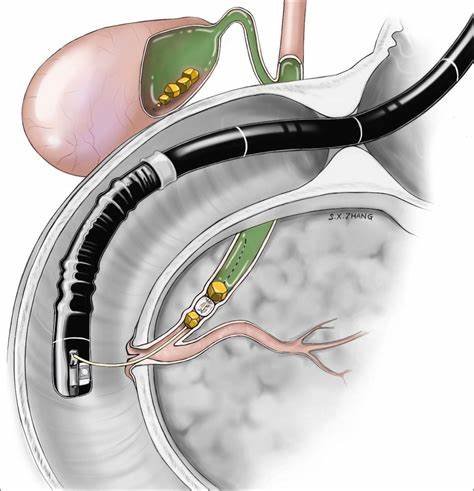

Endoscopic Retrograde Cholangiopancreatography (ERCP) is a specialized procedure used to diagnose and treat conditions affecting the bile ducts, gallbladder, pancreas, and liver. It combines endoscopy and fluoroscopy to visualize the ducts, identify blockages or abnormalities, and treat them in the same session.

What Happens During the Procedure of ERCP?

Sedation & Endoscope Insertion

You will receive sedation to relax, and a flexible endoscope is passed through your mouth into the small intestine.

Cannulation and Dye Injection

A small tube is inserted through the scope into the bile or pancreatic ducts, and a contrast dye is injected for clear X-ray imaging.

Diagnostic Evaluation

X-rays help the doctor identify stones, strictures, or tumors in the ducts.

Treatment Procedure

Depending on findings, the doctor may remove stones, insert stents, or take tissue samples (biopsy).